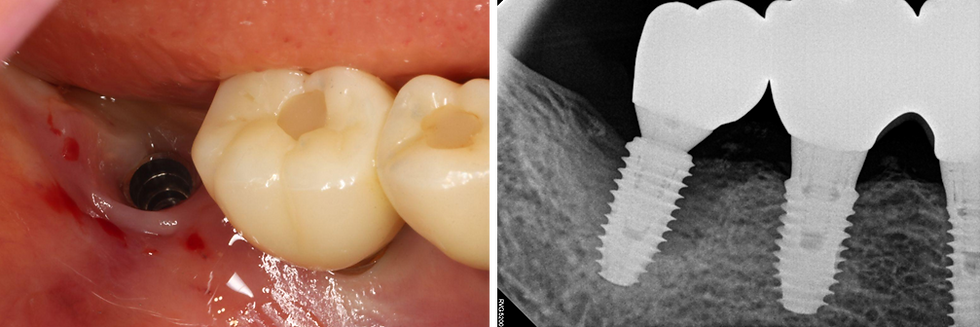

1️⃣Pre-op

Pre-operative intraoral and radiographic findings showing peri-implant inflammation and bone loss at #47.